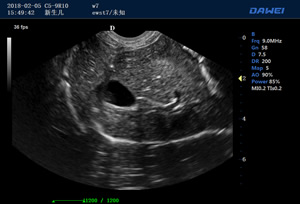

P6-VET便攜獸用彩超機

出色的獸用臨床應用

·支持B、C、PW、CW、寬景成像

·實時三維成像(4D)

適用于各種動物的臨床腹部、胸腔,心臟、肌腱、小器官、眼球、生殖系統等的檢查